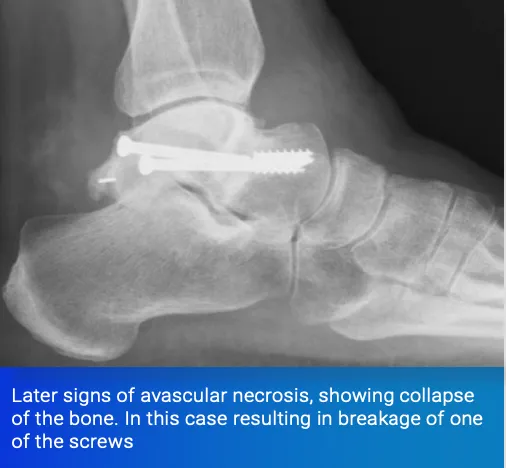

4) Damage to the Blood Supply - Avascular Necrosis

Certain fractures are renowned for damaging the blood supply of the bone. Common examples are fractures of the hip and fractures of the talus, the main bone in the ankle joint.

Talar neck fractures, if caused by a high-energy injury with significant displacement, can completely disrupt the blood supply to the body of the talus. This can cause the bone to die and collapse, resulting in arthritis and may necessitate salvage procedures such as fusions around the hindfoot.